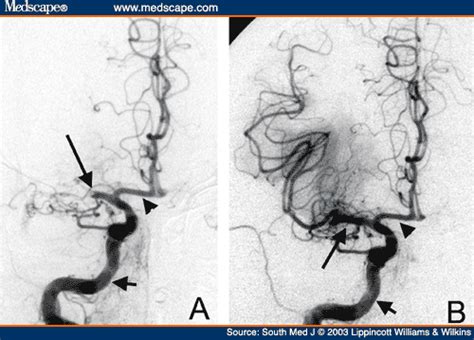

Stroke Cerebral Angiogram - Navigability Trumps All: Stenting of Acute Middle Cerebral ... - A stroke occurs when there is disruption of blood flow to brain tissue, this leads to ischemia (deprivation of oxygen) and potentially infarction (dysfunctional scar tissue).. Preoperative angiograms analyzed in 29 upper brainstem revascularization patients demonstrated stenotic lesions. Cerebral angiography is a procedure that doctors use to image blood vessels in the brain. Description of cerebral angiography (cerebral angiogram). An overview of stroke for patients and caregivers. Moniz showing an angiogram in paris babinski patient died from stroke.

Artery, known as a vascular dissection. Introduction to cerebral angiography and its role in modern diagnostic imaging. A cerebral angiogram may be performed: Unlike most parts of this website, this page is primarily intended neither for the. The purpose of this research study is to collect data/measurements that are routinely collected in standard of care cerebral angiogram. Preoperative angiograms analyzed in 29 upper brainstem revascularization patients demonstrated stenotic lesions. • ischemic strokes result from asvd of the carotid arteries and aortic arch, which embolize thrombi and atherosclerotic material, as well as local atherosclerosis of the cerebral vessels. In india, a stroke occurs once every 40 seconds and every 4 minutes somebody dies of a stroke. Moniz cerebral angiogram of a dog strontium bromide. Nn the neuroradiologist will need to examine all the. A stroke occurs when there is disruption of blood flow to brain tissue, this leads to ischemia (deprivation of oxygen) and potentially infarction (dysfunctional scar tissue). If you've had a stroke, a cerebral angiogram can be used to assess the extent of the damage to the blood vessels. Cerebral angiography is a procedure that doctors use to image blood vessels in the brain.